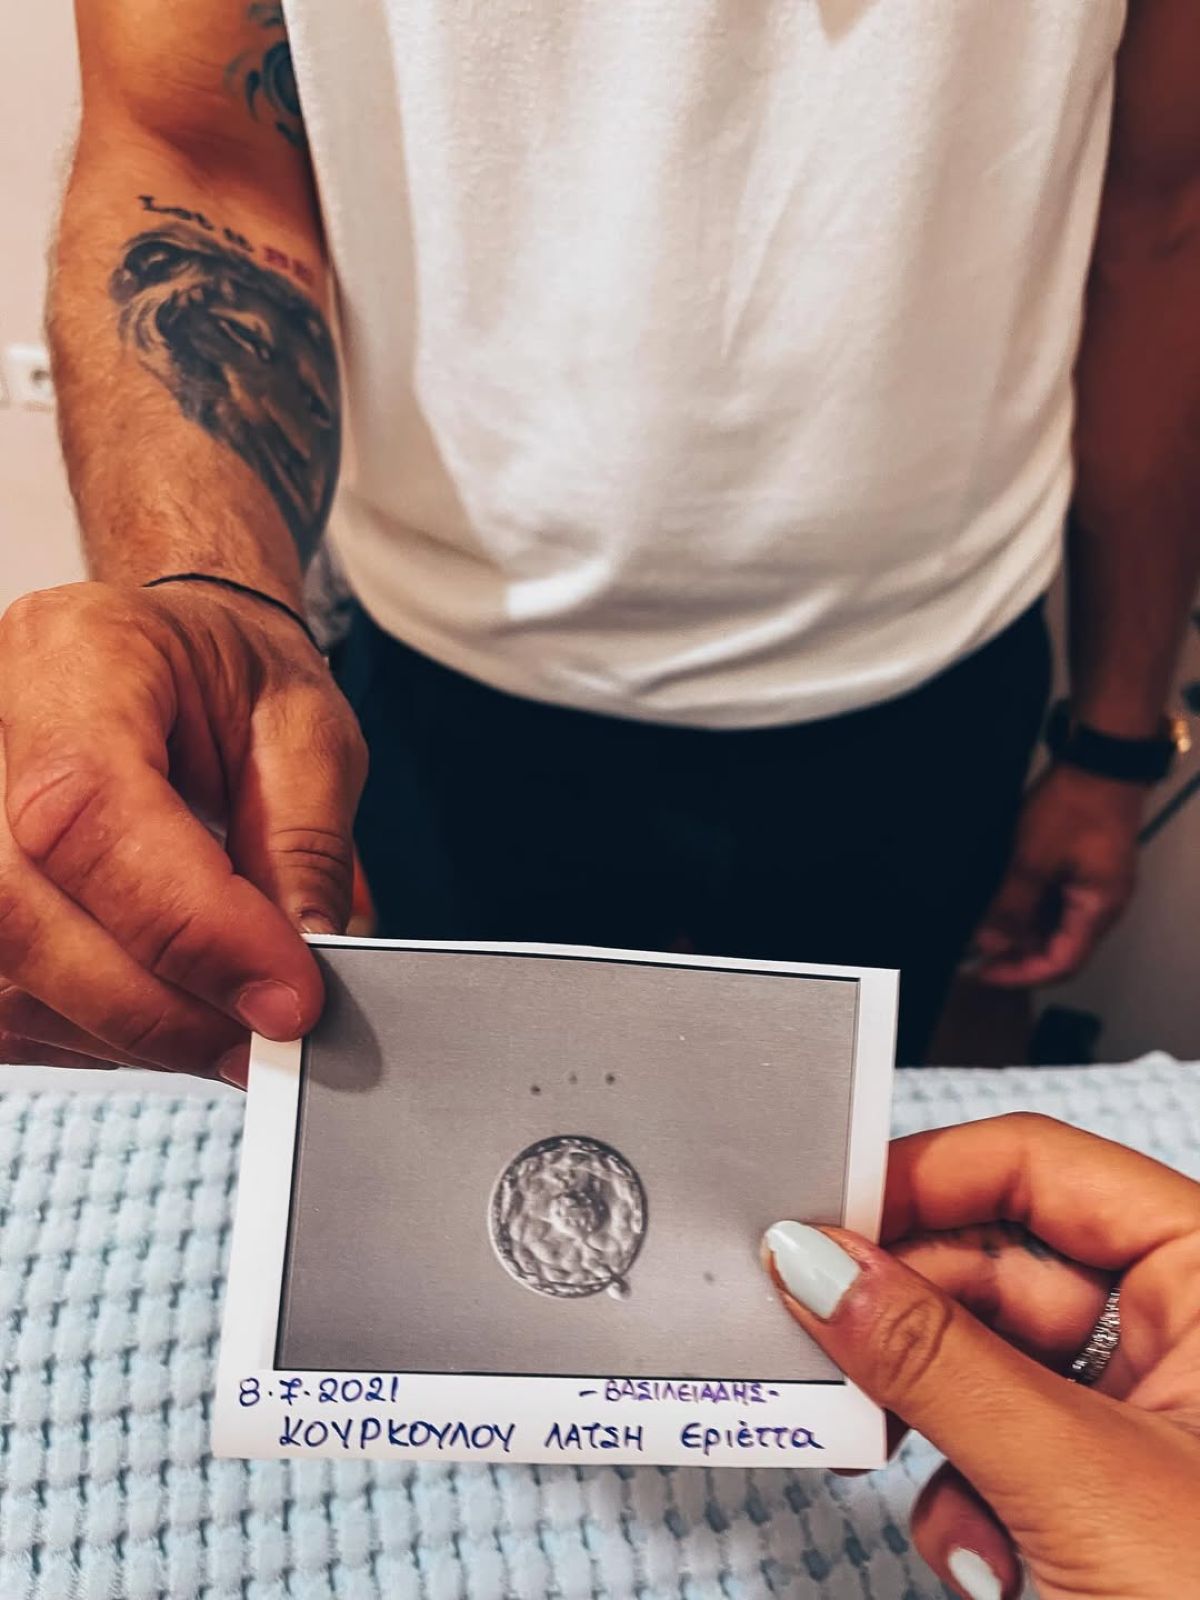

Η Εριέττα Κούρκουλου λοιπόν, έγραψε χαρακτηριστικά: «Η ιστορία σου ξεκινάει πολύ πριν το πρώτο σου κλάμα. Ξεκινάει από την αγάπη. Την αγάπη δυο ανθρώπων που ενώ βρίσκονταν στον κόσμο τους έπεσαν ο ένας πάνω στον άλλον και τελικά αποφάσισαν ότι ήθελαν να κάνουν μαζί ένα παιδάκι. Εκεί αρχίζει το καλό! Προσπάθεια, αποτυχίες, κλάμματα, αγκαλιές, προσευχές, εξετάσεις, γιατροί, χάπια, ενέσεις, απογοήτευση, ελπίδα, έμβρυα και μεταφορά ενός εκ των δώδεκα στις 8 Ιουλίου του 2021.

Αυτό το ένα ήσουν εσύ! Στις 21 Μαρτίου ήρθες και έφερες τα πάνω κάτω και εδώ και τέσσερα χρόνια εκεί παραμένουν – τα ΠΑΝΩ – ΚΑΤΩ! Όταν σου δώσαμε το όνομα των παππούδων σου φοβόμουν μην σε επισκιάσει. Πού να ήξερα τι μας περίμενε… Ένα παιδί ευφυέστατο σε βαθμό που μας τρομάζει, με αρκετά νεύρα, (σπάνιες) αγκαλιές που σε παραλύουν και μια καρδία από χρυσάφι. Ευχαριστώ για τις στιγμές, τα άπειρα μαθήματα και το όνειρο που έκανες πραγματικότητα. Συγγνώμη για τα λάθη που έχω κάνει και εκείνα που θα κάνω στο μέλλον. Υπόσχομαι να σε αγαπάω με όλο μου το είναι για πάντα! Χρόνια Πολλά ★ μου!».